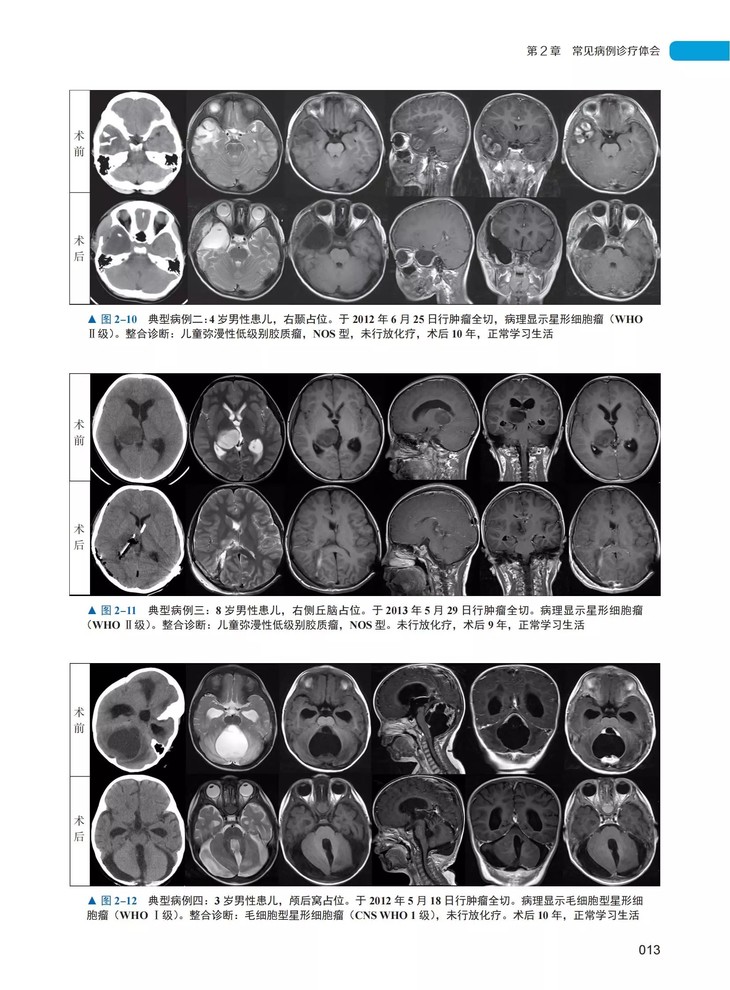

本书由北京天坛医院小儿神经外科主任宫剑教授主编,是继《宫剑小儿神经外科手术笔记 1》之后,宫剑教授及其团队“十年十部手术笔记”出版计划中的第 2 部。宫剑教授专注于儿童颅内肿瘤及各类先天性疾病外科治疗近 20 年,带领团队每年完成手术千余例,数量及质量均达到国际先进水平。本书上篇为每年千余例临床病例中精心挑选的 50例典型病例,详细介绍患儿的主诉、临床症状和体征、术前术后影像学特点、手术操作要点、术后病理及蛋白基因检测结果、术后转归等,结合国内外最新研究进展,总结出该病种的治疗经验与手术体会。下篇则汇总了宫剑教授及马振宇主任接受神外新媒体的最新访谈,就部分病例的天坛诊疗规范进行了详细解读,对小儿神外的历史进行了系统回顾。本书是第一手临床资料总结,实用性强,适合作为日常临床诊疗工作的参考资料,也适于广大患儿家长参考阅读。